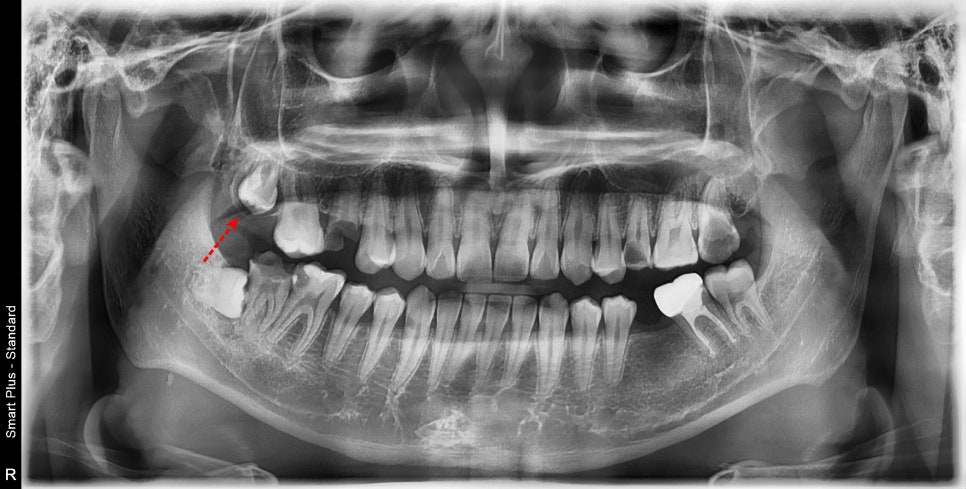

맹출 시기가 지났지만 맹출 되지 않고 치배에 갇혀있는 경우

해당 환자는 성인이 되었지만

알 수 없는 이유로 영구치가 치배에 아직 갇혀있었고

뿌리의 성장이 제대로 이루어지지 않았습니다.

치아의 맹출을 유도해 줄 수 있는 치료가 필요했습니다.

맹출 유도를 하기 위해서는 먼저 잇몸에 길을 내어주고

치아머리에 남아있는 얇은 껍질을 걷어내 주어

치아가 저항 없이 내려오도록 해주는 것이 우선이었습니다.

어릴 적 치배가 영향을 받지 않은 치아라면 해당 치료만으로도 해당 영구치는

정상적으로 맹출이 될 것입니다.

길을 내어주고 3달이 지났습니다.

그동안 안 좋은 치아들을 치료하고 있었습니다.

엑스레이 상으로도 치아는 맹출 되고 있는 것을 볼 수 있습니다.

뿌리도 조금 성장한 것으로 보입니다.

해당 치아는 강한 고정력을 가하지 않고

치근이 성장하며 맹출 되기를 지켜봐야 할 것입니다.